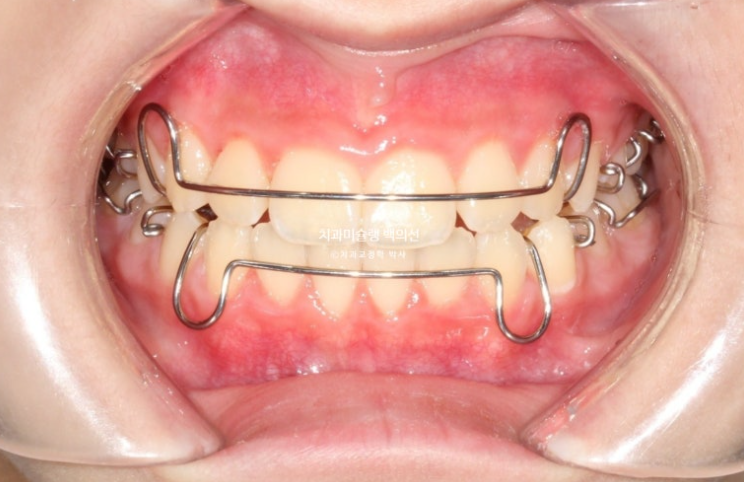

파란화살표 부분을 보자면

장치 양옆에 날개처럼 튀어나온 부분이 Wing 이며 이 부분이 아래턱의 위치를 정상위로 유도합니다.

23.11

사진의 파란화살표처럼 위 아래 윙 끼리 엇갈려 물리며 아래턱을 전방위치 시키며, 최대성장기와 맞물리면 하악골 성장까지 유도하게 됩니다.